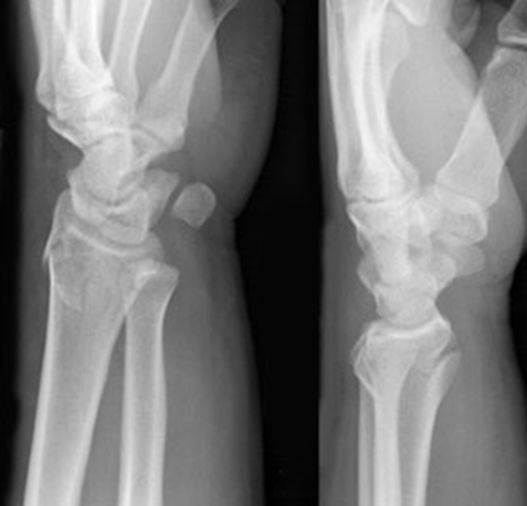

Colles骨折

桡骨远端骨折

骨折向掌侧成角

远折端向背侧移位

Smith骨折

正常腕关节

月骨周围脱位

舟骨骨折